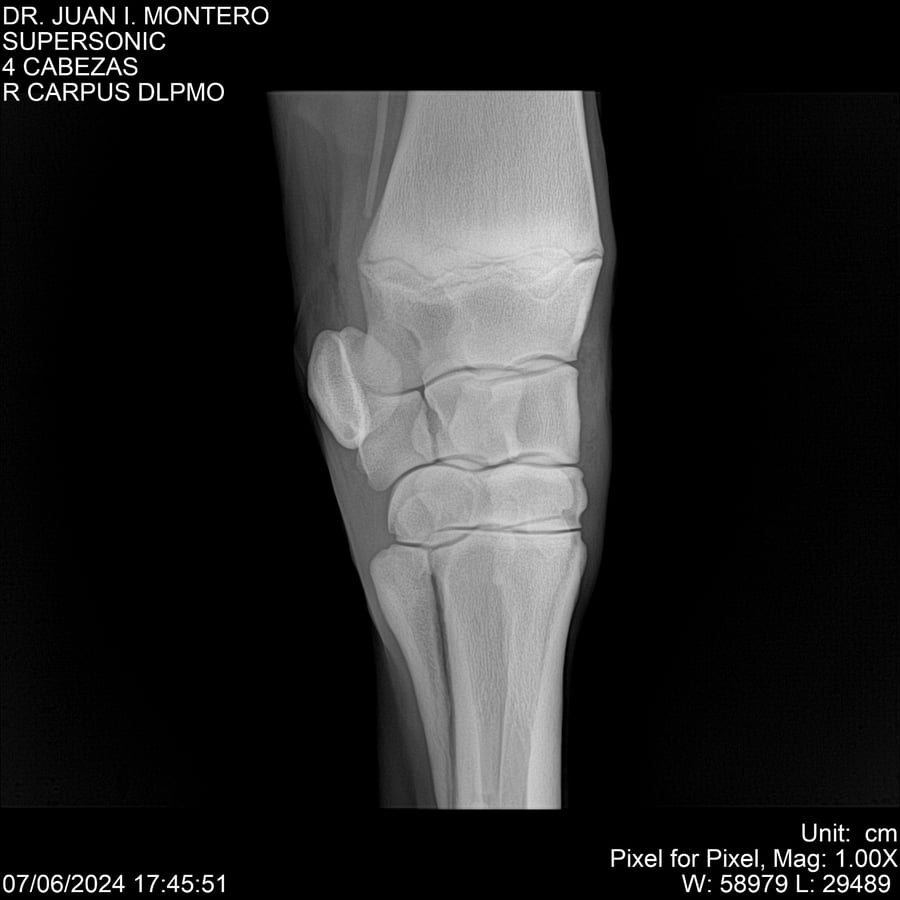

LOTE 5, SUPER SONIC Lote Anterior Volver al remate Lote Siguiente Ficha Contacto Montevideo - Ficha del Lote Identificador: #281089 Categoría: Yeguarizos Montevideo - 69 Visualizaciones ClicData Contacto Empresa: Abelenda N. R., Walter Hugo Nombre*: Teléfono* : E-mail* : Mensaje Enviar Registrese gratis Este contenido Exclusivo está disponible sólo para usuarios registrados Ingresar